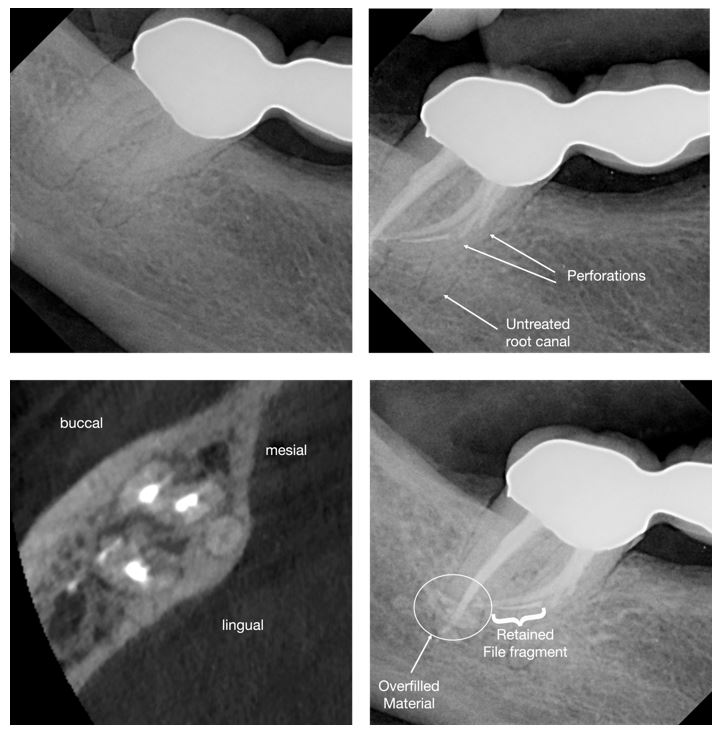

Many shaping mishaps originate during assessment. Two-dimensional radiographs, while indispensable, cannot fully represent three-dimensional root canal anatomy. Severe curvatures, apical bifurcations, S-shaped canals, and unusual molar or premolar configurations are easily underestimated. Small field-of-view CBCT has proven invaluable in complex posterior cases and can meaningfully alter treatment planning before irreversible steps are taken. (Fig. 2)

Instrument fracture remains one of the most anxiety-provoking events in endodontic practice. Yet presence of a retained instrument fragment itself is not synonymous with failure6. The prognosis depends heavily on fragment location, canal anatomy, remaining tooth structure, and the quality of disinfection achieved prior to separation. Aggressive retrieval attempts, particularly without magnification or appropriate training, can convert a manageable complication into perforation, root fracture, or tooth loss.

Figure 2: Clinical example of a mandibular second molar with unusual anatomy. Postoperative radiographs show the presence of a retained instrument fragment along with further procedural errors.